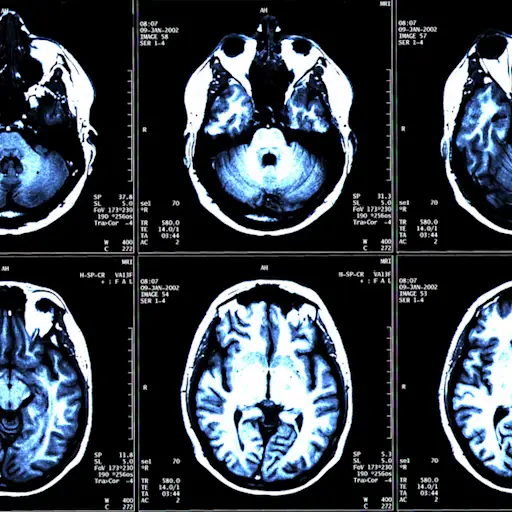

DMTs不是用来帮助日常症状的,所以你不一定能知道它们是否起作用,但是,它的目标是控制你的多发性硬硬症。它的临床术语是显而易见的:“我们寻找的是所谓的‘没有疾病活动的证据’,”翁田田博士说。简而言之,这意味着你不再有多发性硬化症的复发或发作,而且在你的核磁共振上没有任何新的脑损伤的证据。他说:“这是一个非常容易实现的目标,也是我们在所有患者身上努力实现的目标。”

每个人都不一样——你可能会在几周或几个月后感到轻松。科斯特洛说,在你开始使用一种新的多发性硬化症治疗方法后不久,你的医生可能会看你的反应如何。检查通常包括核磁共振成像、实验室工作和身体检查。她说:“大多数提供者都希望密切关注刚开始接受治疗的患者。”她说:“在6到9个月的时间里,你就可以知道病人对某种药物的耐受程度,或者药物是否出现了次优反应。”